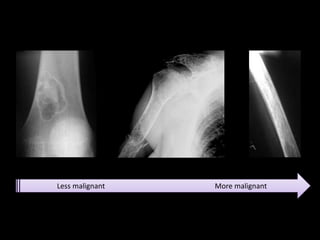

Geographic Bone Destruction

• Destructive lesion with sharply defined border

• Implies a less-aggressive, more slow-growing, benign

process

Moth-eaten Appearance

• Areas of destruction with ragged borders

• Implies more rapid growth

• Probably a malignancy

Permeative Pattern

• Ill-defined lesion with multiple

“worm-holes”

• Spreads through marrow space

• Wide transition zone

• Implies an aggressive malignancy

Less malignant More malignant